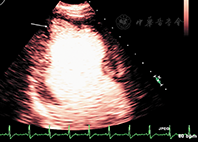

LVEF的准确测量对心血管疾病患者的治疗极为重要,对预测心肌梗死后及血运重建后充血性心力衰竭患者的不良事件具有重要价值。超声心动图是目前唯一能够床旁提供实时动态连续心脏解剖结构和功能动态评估的可视化医学影像技术方法,与其他影像技术相比,具有无电离辐射、容易获取、便携和成本相对较低的优势。已有研究发现常规的非增强超声心动图测量的LVEF与公认的金标准相比有显著差异,观察者间一致性低,因此严重影响了常规超声心动图心功能测量的实用性和可靠性。最近的一些研究表明,造影超声心动图测量左心室容积和LVEF与核素显像、MRI、CT有着良好的相关性,并且提高了观察者间的一致性及医师诊断信心[21,22,23](图3)。

在临床需要精确定量评估左心室容积和LVEF的情况时,如需要进行动态左心室功能评估(接受化疗、已知心脏衰竭患者在临床状态变化时的重新评估、心肌梗列后重构、心脏移植、瓣膜反流患者瓣膜置换术的时机确定、评价是否应当安置心内装置等),可以考虑使用造影检查[24]。

在左心室完全显影且无心尖部造影剂显影漩涡及基底段衰减现象时才能进行节段室壁运动分析和测量LVEF。当缓慢造影剂弹丸给药出现心尖造影剂漩涡现象时,使用实时超低MI成像、提高造影剂输注速度或将聚焦置于心尖部可获得图像改善。